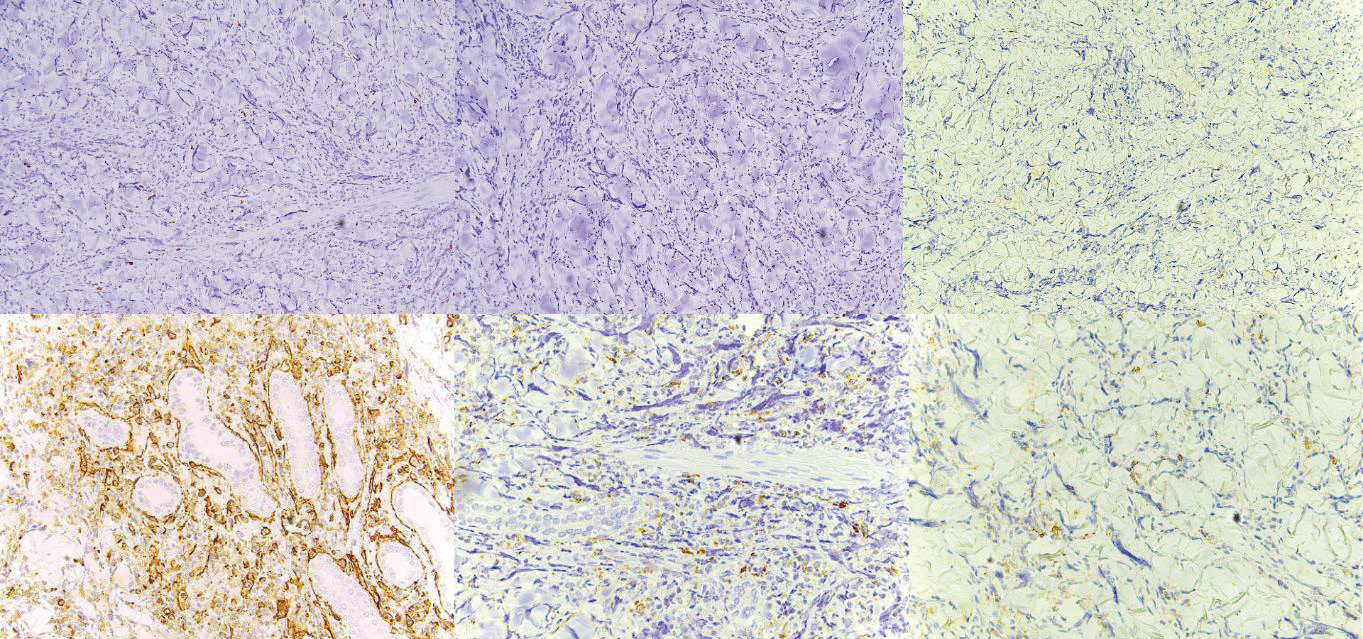

On dermatologic examination, the patient presented with multiple, discrete, round, firm, erythematous to violaceous papules and plaques on the chest, back, and bilateral upper and lower extremities [Figure 1]. The initial clinical differential diagnoses were leukemia cutis, erythema nodosum, fixed drug eruption, arthropod bite reaction, and allergic contact dermatitis. He underwent a 4 mm skin punch biopsy on the chest. Haematoxylin and Eosin-stained sections revealed orthokeratosis, and an acanthotic epidermis that was slightly papillomatous with basal layer hyperpigmentation. In the dermis are diffuse infiltrates of atypical leukemic and myeloblastic cells in between thickened collagen bundles as well as surrounding adnexal structures and neurovascular bundles. [Figure 2]. The specimen was negative for CD3, CD20, Myeloperoxidase (MPO), and CD117 [Figure 3A-D]. Meanwhile, it was positive for CD34 and CD68 (Figure 3E, Figure 3F). The histopathologic examination and immunohistochemical staining were consistent with leukemia cutis.

Figure 3:Immunohistochemistry Staining. A. CD3 negative. B. CD20 negative.

C. MPO negative. D. CD117 negative. E. CD34 positive. F. CD68 positive.

Based on the algorithm proposed by Cronin, et al. for diagnosing

myeloid leukemia cutis, the initial immunohistochemical stains to

be performed are CD3 and CD20 [12]. These markers are typically

negative in myeloid leukemia cutis, which aligns with the findings

in this patient’s case. The subsequent recommended stain is CD43,

which tends to be positive in nearly all cases of myeloid leukemia

cutis. However, this stain was not conducted in this case. The status

of MPO staining can vary, being either positive or negative in myeloid

leukemia cutis. In instances where it is negative, as observed in this

patient, CD68 may be requested. CD68 is generally positive in cases

of myeloid leukemia cutis. In line with this, the CD68 result in this

patient was indeed positive. Subsequently, CD56 may have been

considered. Similar to MPO, CD56 can be positive or negative. When

CD56 is negative, CD117 might be requested, and a negative result

would be indicative of myeloid leukemia cutis. Notably, this pattern

is consistent with the results in this case. It is worth mentioning that

the algorithm does not include CD34. A positive CD34 result suggests

the presence of myeloid or monocytoid leukemia cutis, specifically

granulocytic sarcoma. This outcome aligns with the observations in

this patient’s case.